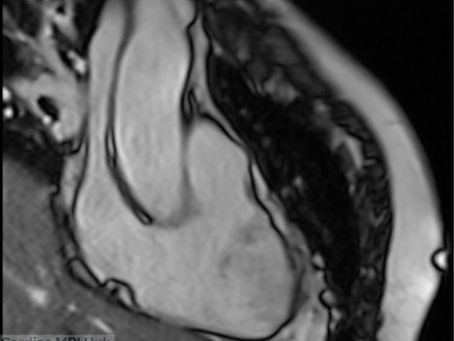

Understanding the Left Ventricle Short Axis View: Comprehensive Cardiac MRI Planning for Technologists

The short axis (SAX) stack is the definitive approach for evaluating the LV in cardiac MRI. The left ventricle short-axis cine stack is acquired perpendicular to the long axis of the heart, extending contiguously from the mitral valve plane at the base down to the true apex. Coverage should allow complete assessment of the LV myocardium and accurate volumetric analysis in both end-diastole and end-systole. Short Axis Planning The short axis view will align perpendicular to th

Proper sampling of the left ventricle in short axis orientation at base, mid, and apex levels is essential for technologists to master. Understanding the unique anatomy at each level ensures precise volumetric quantification and comprehensive wall motion analysis. Short Axis Sample (Base Mid Apex) Short axis left ventricle sample (Base, Mid, Apex) slices shown above. The base slice to left is too close to LVOT, want to see full circle of myocardium shown in image on right. Th